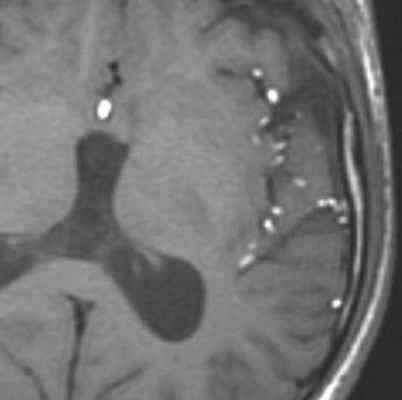

Эпидермоидные кисты (эпидермоиды) – доброкачественные врождённые образования. Они происходят из эктопических эпидермальных клеток и развиваются в период закрытия, в 3-5 нед. эмбриогенеза, как следствие неполного разделения нейрональной и покровной эктодермы. Частота составляет около 1% от внутричерепных образований. Обычно диагностируются в возрасте 25 – 45 лет. Локализация эпидермоидов может быть любой, но типичная – мосто-мозжечковый угол (третье по частоте образование этой области), предмостовая цистерна, параселлярная область, четверохолмие и желудочковая система, очень редко в полушариях, спинном мозге и интрадиплоидно. Растут они интра- или экстрадурально, экспансивно, медленно, сдавливая ствол мозга, внутричерепные нервы, но не разрушая кость. Иногда захватывают сосуды и нервы. По характеру роста их можно отнести к опухолевидным образованиям. Вокруг эпидермоидов нередко развивается асептическое воспаление, а при разрыве содержимое (жир, кератин) прорывается в ликворные пространства. Клинические проявления зависят от локализации и масс-эффекта.

При МРТ головного мозга картина неспецифическая и зависит от содержимого кисты. Если она не содержит жира, топри МРТ головного мозга эпидермоидная киста имеет ликворную интенсивность сигнала. В таком случае эпидермоидная киста трудно отличима от арахноидальной, хотя, как правило, не столь однородная. На FLAIR томограммах и диффузионно-взвешенных МРТ головного мозга содержимое эпидермоидов светлее ликворного. Жировое содержимое, такие эпидермоиды еще называют холестеатомой, приводит к высокому сигналу на Т1-зависимых МРТ головного мозга. Видимо, он обусловлен липидами, но не холестеролом. На Т2-взвешенных МРТ головного мозга он менее интенсивен чем ликвор. Контуры эпидермоидов на МРТ всегда четкие. Холестеатомы составляют всего 3-5% от эпидермоидов. В 15-20% случаев встречается кальцификация по переферии кисты. Редко наблюдается усиление стенок кисты при МРТ головного мозга с контрастированием.

Арахноидальные кисты представляют собой скопление ликвора между листками расщепленной паутинной оболочки. Арахноидальная киста обычно не сопровождается другими мальформациями. Незначительная часть арахноидальных кист имеет приобретенное происхождение – следствие лептоменингита, операции или кровоизлияния. Частота составляет около 1% от внутричерепных образований. Соотношение полов М:Ж, как 4:1. Типичная локализация – средняя черепная ямка (в области Сильвиевой борозды 50%), межполушарная щель, мосто-мозжечковый угол (11%), за скатом или на уровне четверохолмия (10%), в области червя мозжечка (9%), реже в области межножковой и предмостовой цистерн (3%), а также супраселлярной и хиазмальной цистерн. В зависимости от размера предложено делить кисты на 3 типа (Galassi, 2006), что однако, не имеет практического значения. Ретроцеребеллярная арахноидальная киста довольно часто встречаются за мозжечком и отличима от mega cisterna только по неизменённой задней черепной ямке. При МРТ головного мозга содержимое кисты чисто ликворное, стенки гладкие, чётко очерченные, внутри кисты могут быть перегородки. Мелкие арахноидальные кисты очень трудно увидеть при МРТ головного мозга. Меняя ширину окна и его уровень на Т1-зависимых МРТ изображениях можно заметить, что киста чуть светлее ликвора. Дифференциальная диагностика с эпидермальными кистами лучше осуществляется с помощью МРТ последовательности FLAIR. На них при МРТ головного мозга эпидермальные кисты становятся яркими, в отличие от гипоинтенсивных арахноидальных. Вероятно, вариантом арахноидальной кисты является нейроэпителиальная киста, которая при МРТ головного мозга имеет типичное расположение в области хориоидальной щели.